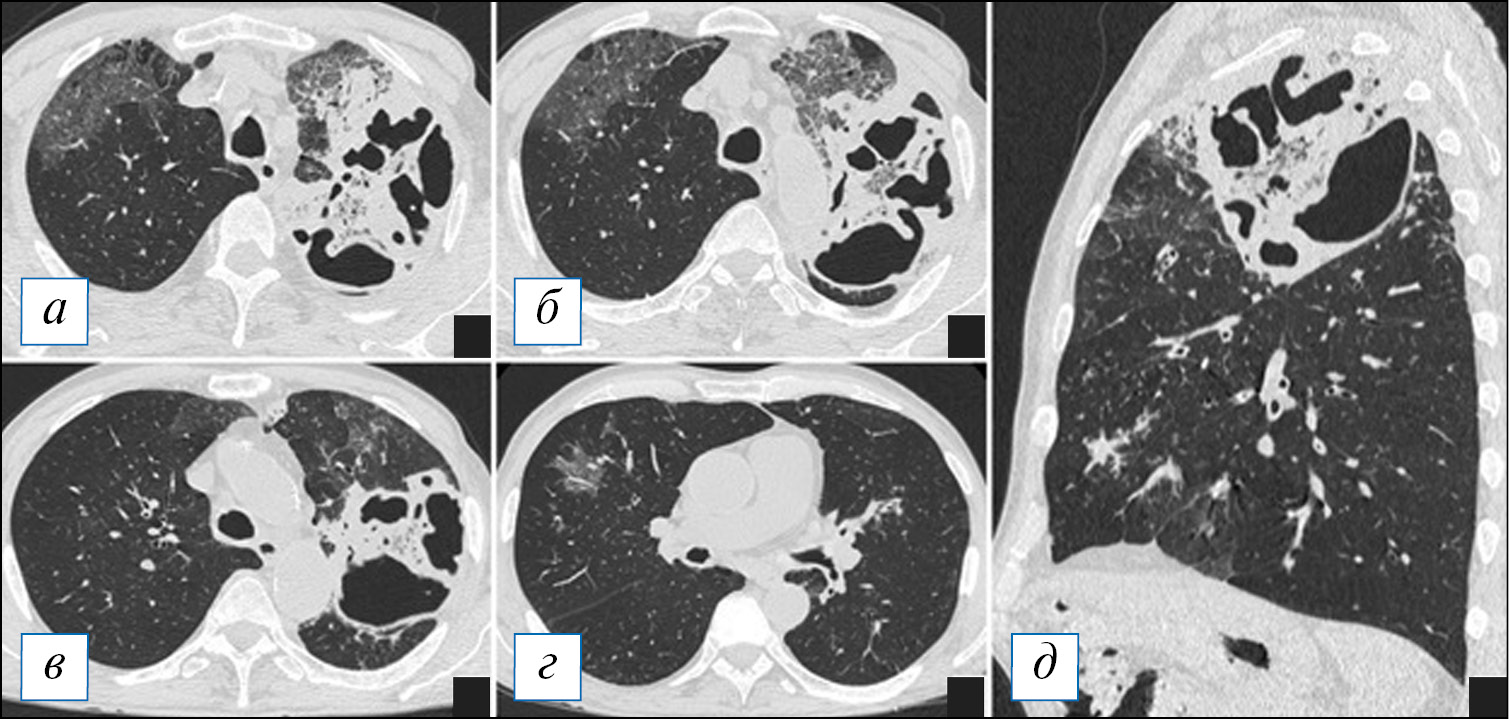

При КТ во время формирования абсцесса выявляют участок уплотнения легочной ткани без четких контуров. В дальнейшем за счет формирования капсулы и рассасывания перикавитарной инфильтрации контуры абсцесса становятся более четкими. Некротический инфильтрат имеет мягкотканную плотность, однородную структуру, просветы бронхов в нем не видны, при этом просвет соответствующего долевого бронха не изменяется. Часто можно увидеть типичный обрыв сегментарных бронхов или их ветвей внутри гнойного инфильтрата. Форма абсцесса при небольших его размерах округлая или овальная. В случае расположения абсцесса над междолевой плеврой определяется симптом ее «провисания» в зоне наибольших некротических изменений (рис. 8, б). Возможно наличие реактивного плеврального выпота.

Рис. 8. Компьютерная томография органов грудной клетки в аксиальной (а–г) и сагиттальной проекциях (д). Формирующиеся абсцессы в обширном инфильтрате верхней доли левого легкого. После внутривенного контрастирования имеются участки пониженной плотности (стрелки), представляющие собой гнойные отграниченные фокусы, которые в дальнейшем с большой вероятностью превратятся в абсцессы. По границе данных фокусов контрастирование несколько усилено, что может говорить о формировании пиогенной мембраны. [Изображения из архива авторов]. / Fig. 8. Axial (а–г) and sagittal (д) chest CT images. Forming abscesses in the extensive infiltrate of the upper lobe of the left lung. After an intravenous contrast enhancement, there are areas of reduced density (arrows), which correspond to purulent delimited foci, likely to turn into abscesses. Along the border of these areas, the contrast is somewhat enhanced, which may indicate the formation of a pyogenic membrane. [Images from the authors’ archive].

Нередко в зоне некроза и гнойного расплавления видны мелкие пузырьки воздуха. По периферии может выявляться полоса окружающей инфильтрации, в которой обычно видны просветы мелких бронхов. После внутривенного введения контрастного препарата плотность центральной зоны некроза не изменяется (остается гиподенсной), а плотность окружающей ткани, представленной пневмоническим инфильтратом и ателектазированной тканью легкого, повышается на 10–30 HU (см. рис. 8) [5, 53]. Эта разница в плотности иногда бывает видна и при нативном сканировании, что является важным дифференциальным моментом, который позволяет судить о формировании абсцесса еще до его дренирования в бронхиальную систему и появления там газа.

После частичного дренирования гноя из полости абсцесса формируется хорошо известная лучевая картина — полость с горизонтальным уровнем жидкости, толщина стенок которой зависит от стадии процесса (рис. 9, 10). После начала отхождения гноя через бронхи их стенки рядом с абсцессом могут быть утолщены (как проявление бронхита). При полной санации острого абсцесса возможно постепенное уменьшение в размерах и полное спадение стенок полости в дальнейшем под действием эластических сил легкого с формированием рубцово-фиброзных изменений.

Рис. 9. Компьютерная томография органов грудной клетки в аксиальной проекции (а–г). Типичная картина острого абсцесса. В верхней доле справа имеется полость с содержимым, при этом наружная и внутренняя стенка полости с достаточно четкими контурами, перикавитарная инфильтрация выражена слабо. [Изображения из архива авторов]. / Fig. 9. Chest CT, axial projection (а–г). A typical picture of an acute abscess. In the upper lobe on the right there is a filled cavity the outer and inner wall of the cavity having fairly clear contours, pericavitic infiltration is poorly expressed. [Images from the authors’ archive].

Рис. 10. Компьютерная томография органов грудной клетки в аксиальной (а, б) и сагиттальной (в) проекциях. Многокамерный «лестничный» острый абсцесс в верхней доле левого легкого. В абсцессе имеется незначительное количество содержимого, инфильтрация вокруг полости отсутствует. [Изображения из архива авторов]. / Fig. 10. Axial (а, б) and sagittal (в) chest CT images. Multi-chamber «ladder» acute abscess in the upper lobe of the left lung. There is a small amount of fluid in the abscess, and there is no infiltration around the cavity. [Images from the authors’ archive].